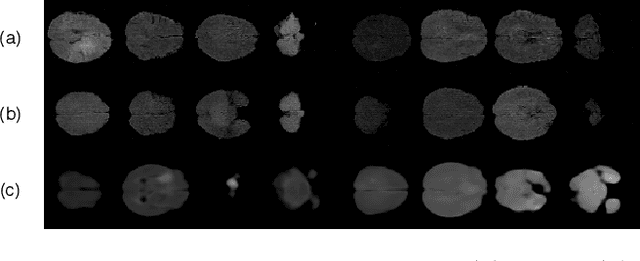

Abstract:Disentangled representations can be useful in many downstream tasks, help to make deep learning models more interpretable, and allow for control over features of synthetically generated images that can be useful in training other models that require a large number of labelled or unlabelled data. Recently, flow-based generative models have been proposed to generate realistic images by directly modeling the data distribution with invertible functions. In this work, we propose a new flow-based generative model framework, named GLOWin, that is end-to-end invertible and able to learn disentangled representations. Feature disentanglement is achieved by factorizing the latent space into components such that each component learns the representation for one generative factor. Comprehensive experiments have been conducted to evaluate the proposed method on a public brain tumor MR dataset. Quantitative and qualitative results suggest that the proposed method is effective in disentangling the features from complex medical images.